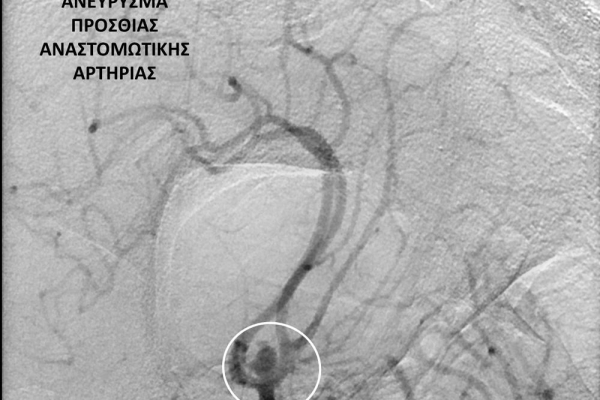

- Η ψηφιακή αγγειογραφία (DSA) αποτελεί την καλύτερη μέθοδο διάγνωσης των αγγειακών παθήσεων.Η αγγειογραφία γίνεται ως εξής: αρχικά παρακεντάται μια αρτηρία πρόσβασης, όπως η μηριαία αρτηρία στη βουβωνική περιοχή ή η βραχιόνια αρτηρία στο βραχίονα. Στη συνέχια προωθείται ένας καθετήρας προς την περιοχή του ενδιαφέροντος και γίνεται η έγχυση σκιαγραφικής ουσίας (σκιαγραφικού) με συνεχή λήψη «εικόνων» των αγγείων-στόχων.